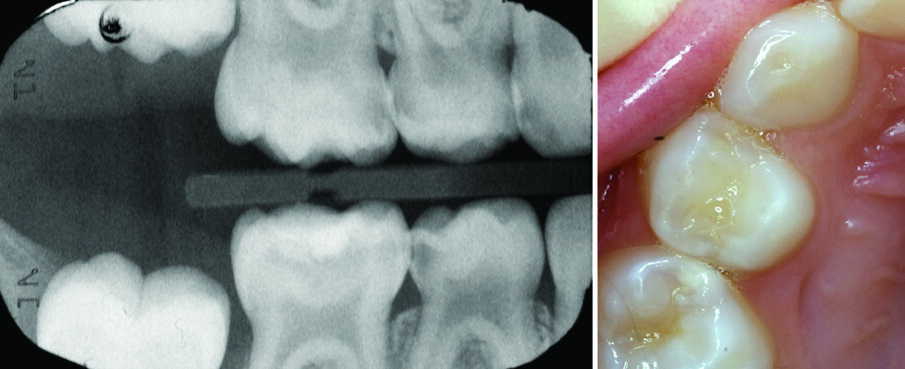

Figures 3 (a, b, c, d): The conventional specialist paediatric dentist approach: The SSC is sized up and trialed (Figure 3a), The rubber dam is removed and the SSC is cemented with a glass ionomer (Figure 3b). Figures (3 c & d) show upper and lower arches restored conventionally with SSCs using LA, rubber dam & high speed drills. Compare these with the teeth in Figure 10

Figures 4 (a) and 4 (b): The Hall technique: Case selection: Figure 4a: Right Bitewing radiograph shows dentinal caries in teeth 53, 54, 55, 85, 84. Tooth 54 will be used as an example here (All the Es and Ds eventually received SSC using the hall technique). Figure 4b: The same lesion of 54, seen in 4a, is not visible clinically.